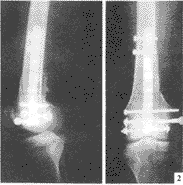

(三)切開復位和內固定 適用於復位不理想或斷端間有軟組織嵌夾,或有血管神經禹傷者可作切開復位。固定方法可用髓內釘或鋼板螺絲釘,同時,適當考慮套用外固定,要求達到固定確實可靠的原則。

(1)股骨上1/3或中上1/3骨折多採用髓內針固定。此法具有術後不用外固定及早期下床活動的優點。過去用開放式打入髓內針的方法,近十年來已被X光電視機(XTV)控制下,僅在穿針處作小切口,不顯露骨折端的閉合穿針方法所代替。閉合法較開放損傷小,出血少,不破壞骨折端的血液供給,有利於骨折癒合。

(2)股骨中1/3或中下1/3骨折,傳統方法是採用6-8孔接骨板螺絲釘固定及髖人字石膏固定。目前多採用加壓鋼板活動。加壓鋼板有多種類型,60年代開始套用加壓器的加壓鋼板固定,其後出現自身加壓鋼板固定沿用至今。有關股骨幹骨折手術及內固定材料選擇,要嚴重掌握適應症,不可濫用。要力求手術成功,防止感染及骨折不癒合的發生。